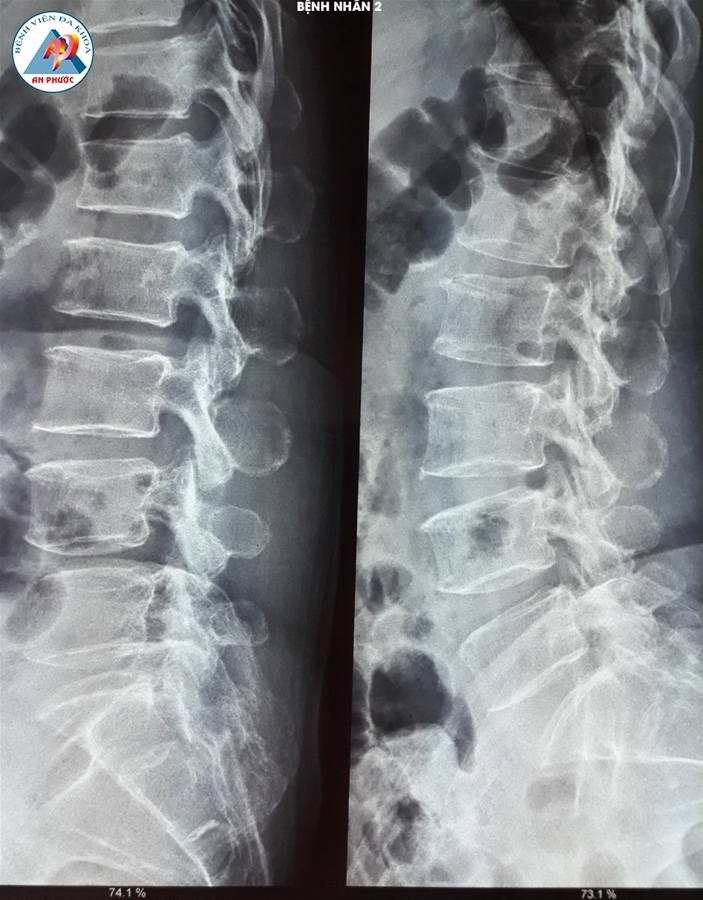

Trường hợp 2: Bệnh nhân nữ, 58 tuổi, ngụ tại Bảo Lộc - Lâm Đồng. Vào viện với tình trạng đau lưng, tê bì chân phải. Bệnh nhân có điều trị nội khoa và tập vật lý trị liệu hơn 06 tháng, nhưng bệnh không giảm.

Qua thăm khám lâm sàng và chụp MRI, XQ CSTL với kết quả: Thoát vị đĩa đệm L4-L5, kèm theo loãng xương nên được chỉ định phẫu thuật lấy nhân đệm và làm cứng L4-L5 bằng nẹp vis, thay đĩa đệm nhân tạo.

Sau mổ 07 ngày, bệnh hết tê chân phải hoàn toàn. Đi, đứng, hoạt động bình thường và đã xuất viện.